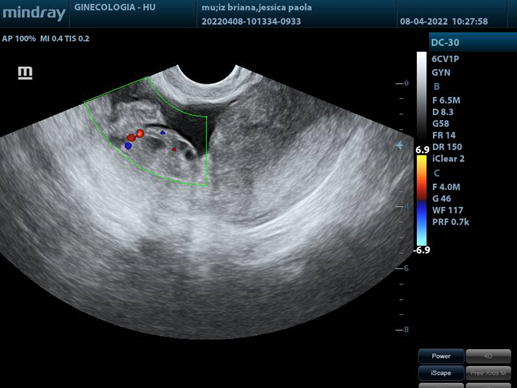

Transvaginal USG: uterus in AVF 4.5x5x3.3cm, LE 12.3mm. Right ovary: 4.8x3.6x3.7 cm vol. 34cc, with a tumor measuring 11.2x8.6cm, solid, with homogeneous and hypoechoic echotexture, with posterior acoustic shadow and Doppler flow uptake. Left ovary: 5x5x2.2cm vol. 19.6cc.

1. Right adnexa with a deep flow of doppler color.